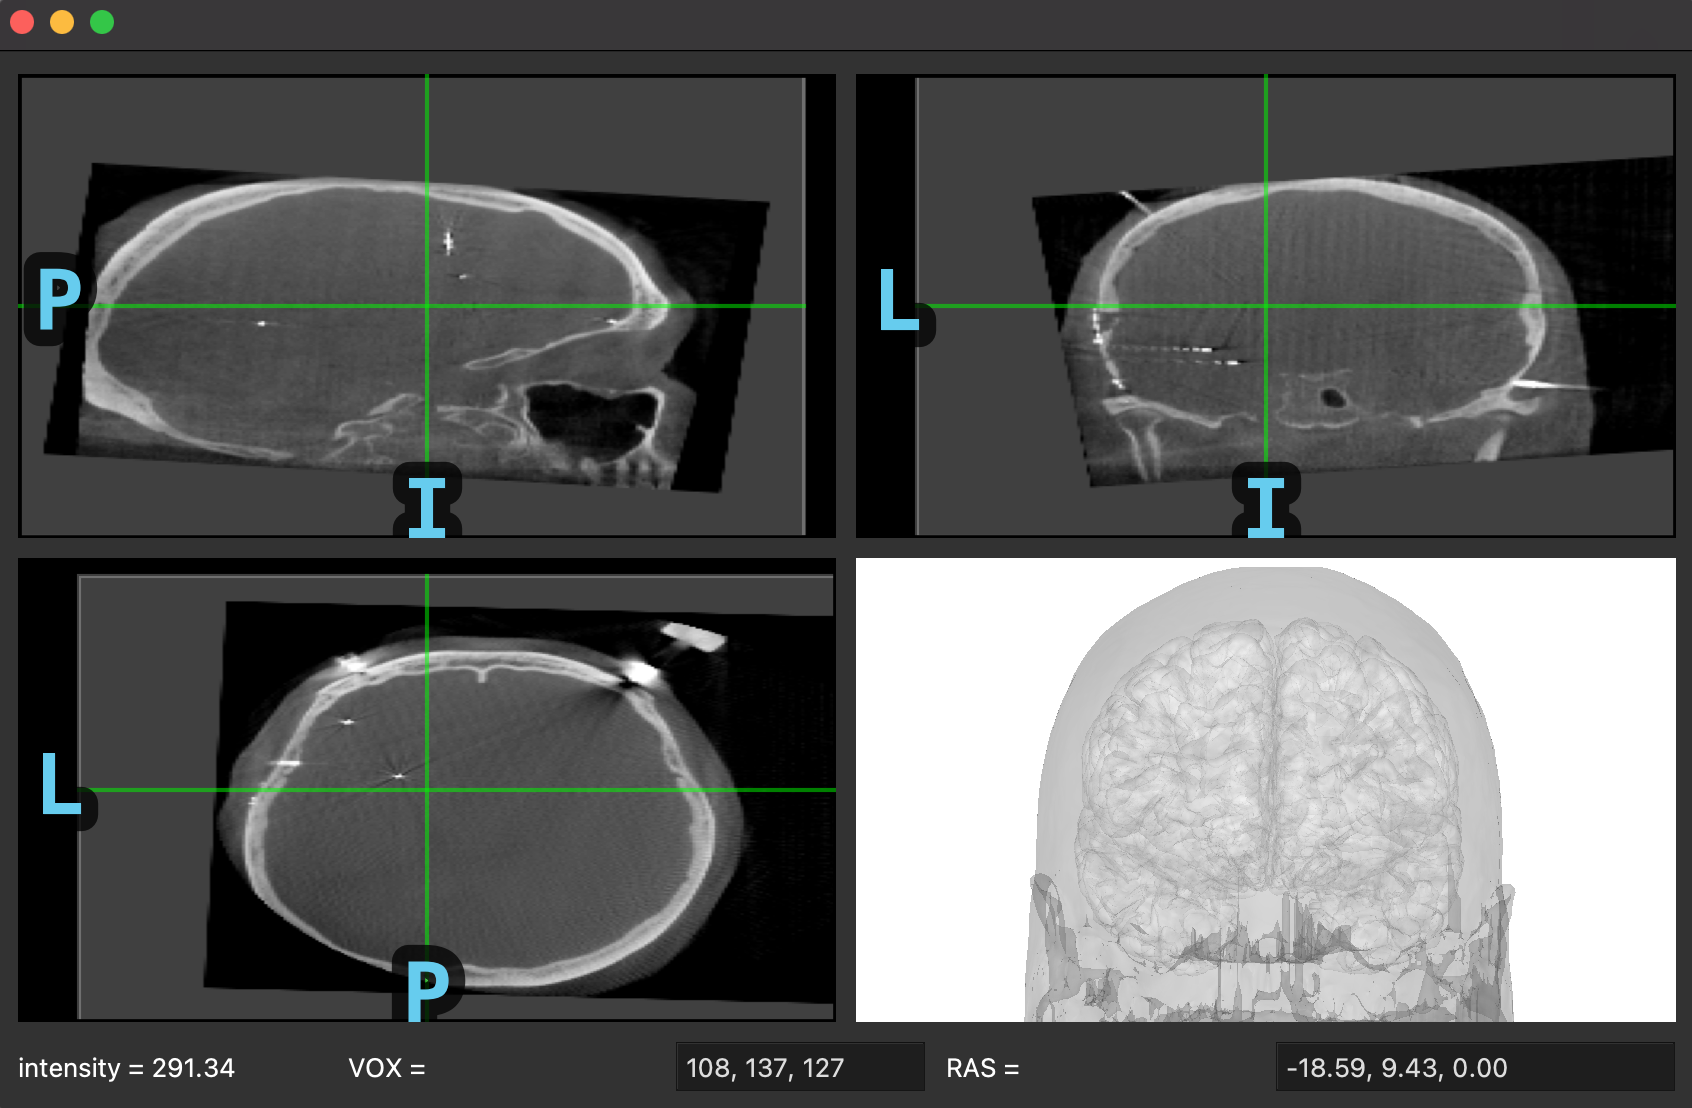

Here's what it looks like, which would be inserted into any GUI and then the extra visualization is added on the top/bottom/sides:

Screen Shot 2022-06-15 at 4 43 09 PM

I was thinking for the TFR viewer the spectrograms/time courses could either be to the side split 50/50 with a smaller slice-browser as in here image or between the bottom bar and the slices. Testing changing the window size, keeping proportionality handles much better making the slice browser horizontally narrower so I think option 1 will probably look better. Then buttons to change from power to ITC to time course could be in that panel on the right as well as changing vmin/vmax etc.